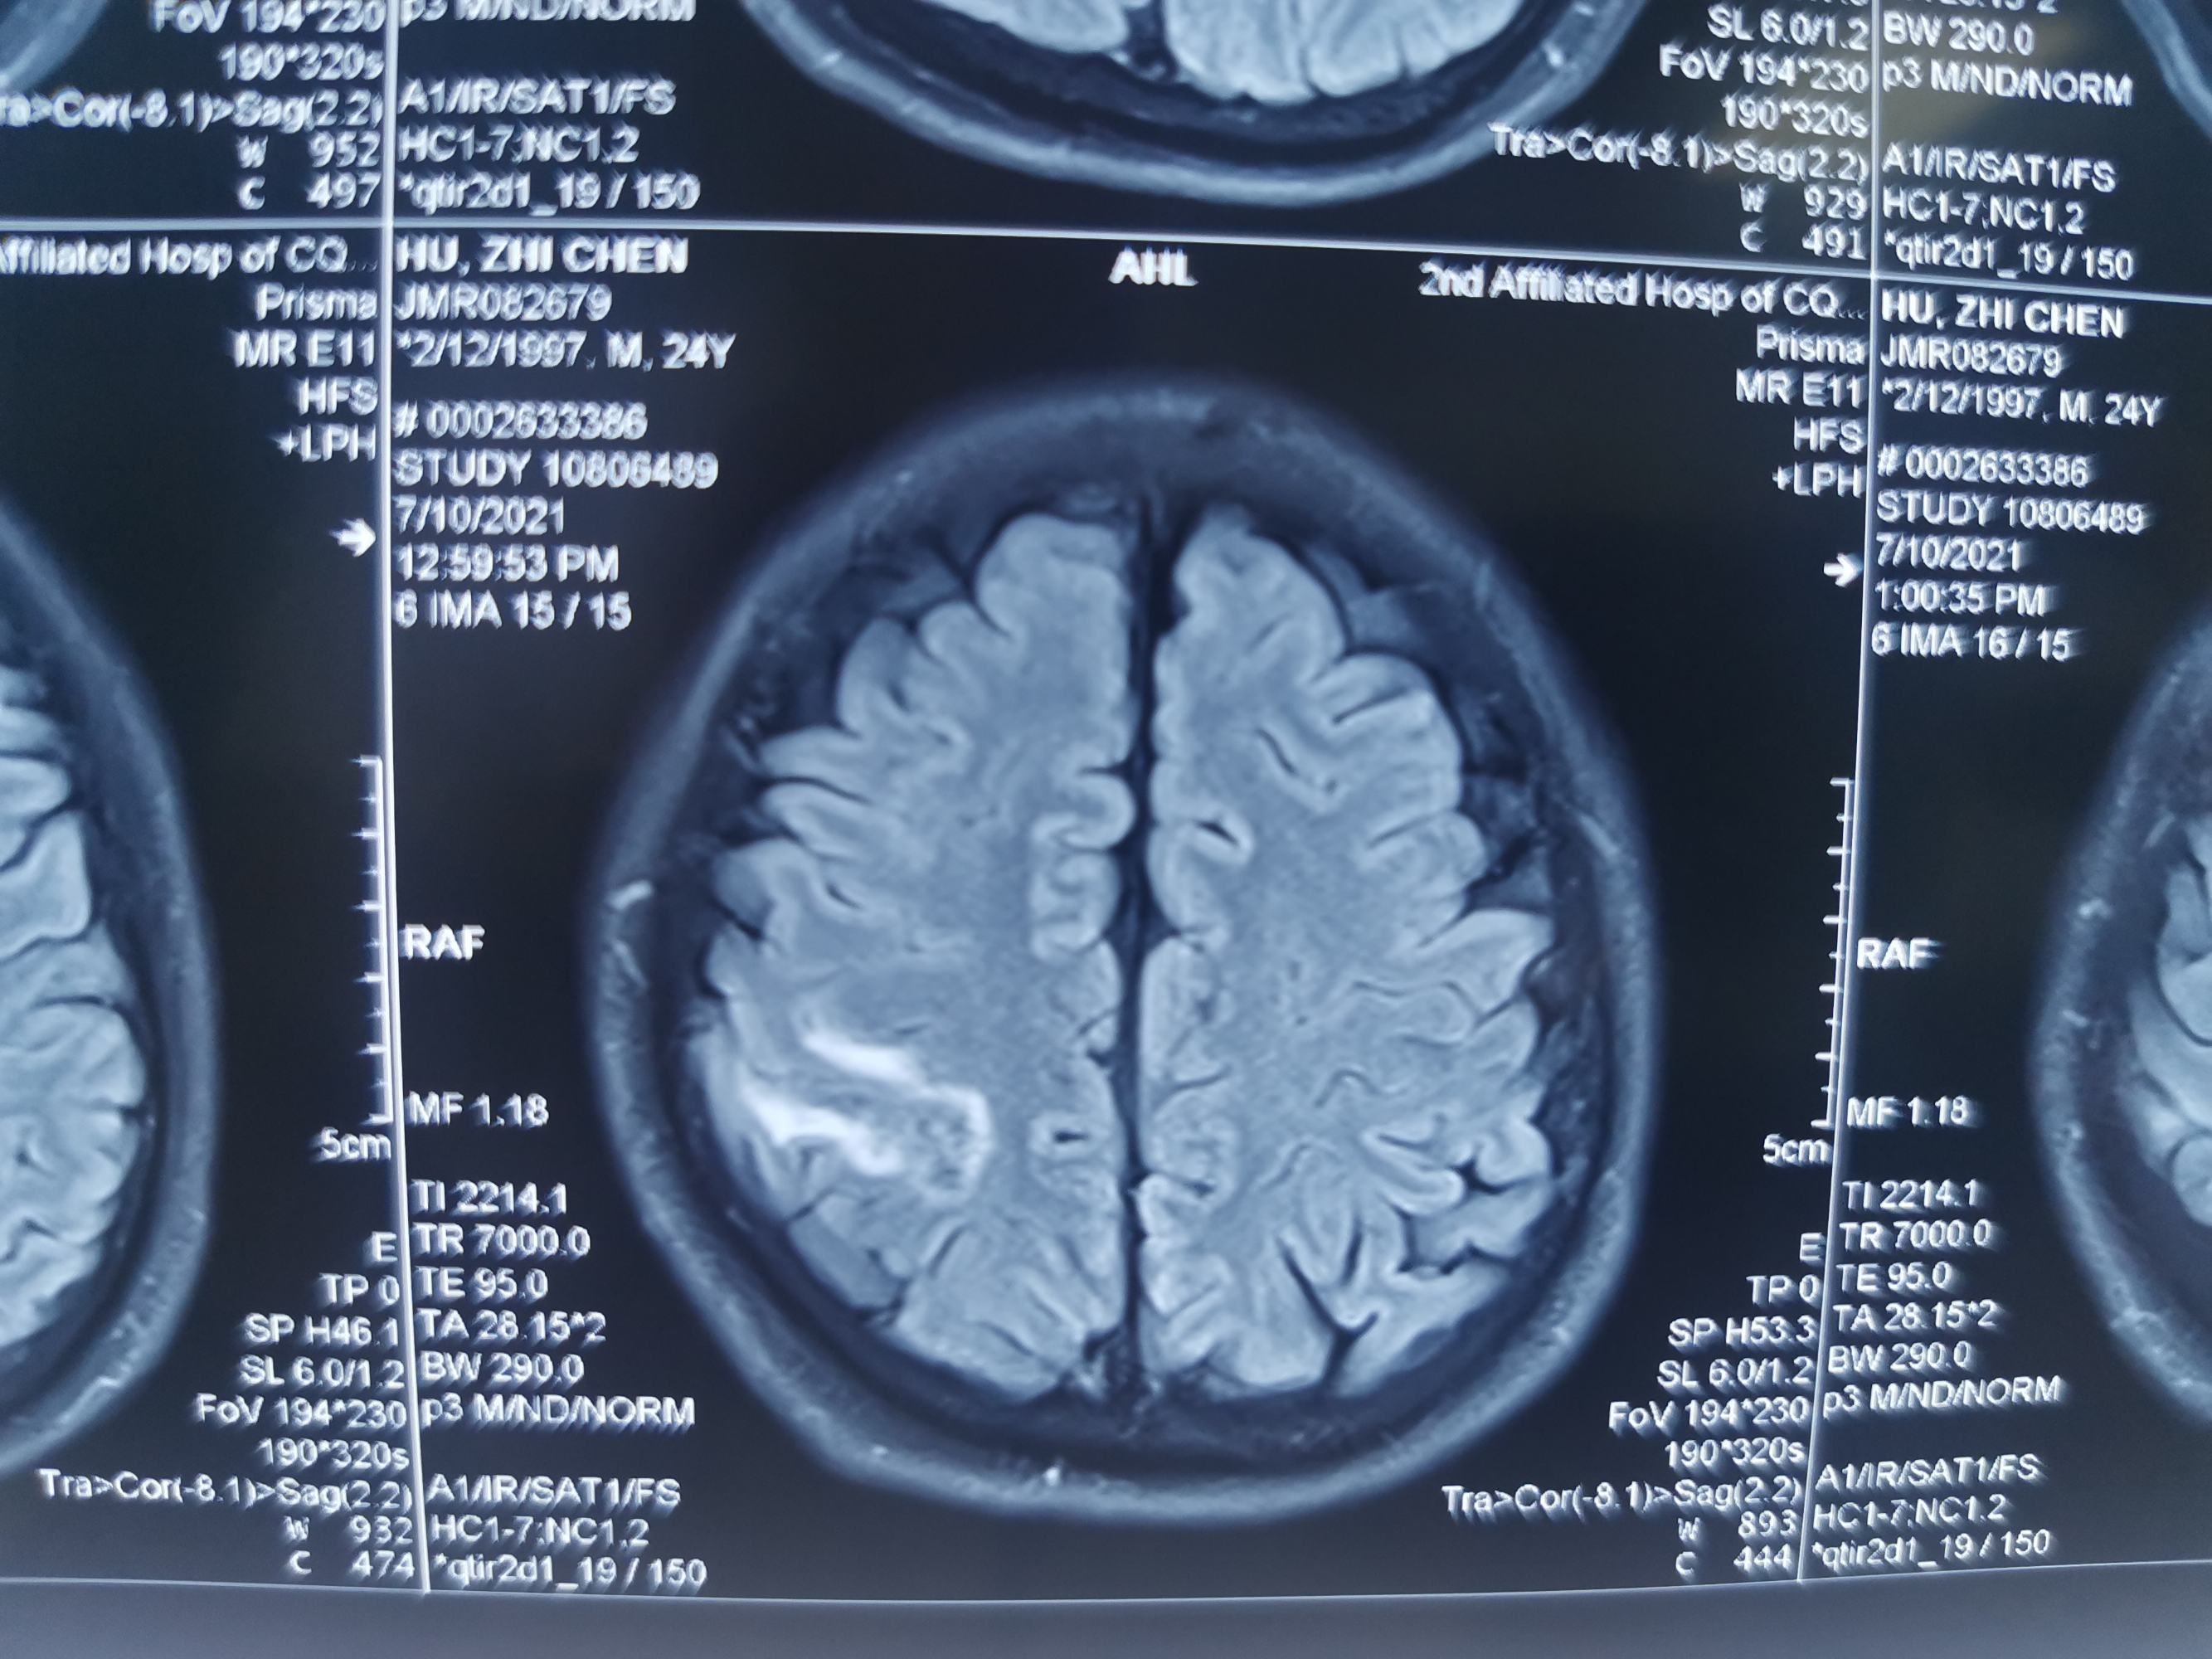

入院后急查头颅磁共振发现顶叶又新发两个病灶。

磁共振发现顶叶又新发两个病灶

DWI考虑新发病灶为脑梗死,考虑该梗塞病灶位于运动皮层导致患者右下肢完全偏瘫。

磁敏感成像考虑首发病灶为出血。

增强显示矢状窦长节段充盈缺损,D-2聚体大于正常上限5倍以上。我科诊断考虑上矢状窦血栓形成伴多发多次脑梗死伴出血。